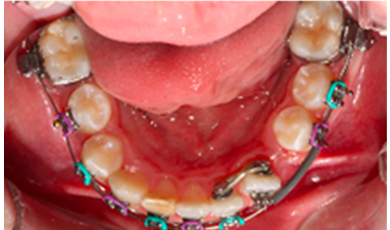

Evolução do tratamento ortodôntico

Evolucao do tratamento ortodontico ja com a instalacao do apararelho fixo em alguns dentes auxiliando o tracionamento do dente incluso.

Evolucao do tratamento ortodontico com o apararelho fixo colado em todos os dentes inferiores e o elemento 33 ja melhor psicionado.

Canino inferior aparente

Inclusão do canino inferior esquerdo no arco, agora nāo mais incluso.